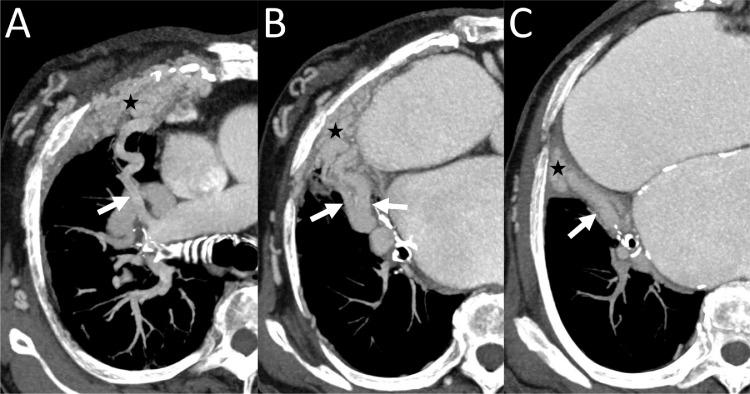

A 74-year-old woman presented with progressive dyspnea. Computed tomography revealed a large systemic artery-to-pulmonary artery vascular malformation (VM) on the right chest wall. Embolization of the VM was performed. First, the main drainers of the VM were retrogradely selected from the segmental pulmonary arteries and embolized using microcoils. Second, 2 main feeders of the VM were selected and embolized with N-butyl cyanoacrylate. Thus, marked flow reduction in the VM was achieved, and the patient's symptom improved dramatically. We believe that embolization of both feeders and drainers is an effective technique for treatment of a chest wall systemic artery-to-pulmonary artery VM.

摘要

一名74岁女性因进行性呼吸困难就诊。计算机断层扫描显示右胸壁存在一个大型体动脉至肺动脉血管畸形(VM)。对该VM进行了栓塞治疗。首先,从肺段动脉逆行选择VM的主要引流血管,并用微线圈进行栓塞。其次,选择VM的2条主要供血血管,用氰基丙烯酸正丁酯进行栓塞。由此,VM内的血流显著减少,患者症状明显改善。我们认为,对供血血管和引流血管同时进行栓塞是治疗胸壁体动脉至肺动脉VM的有效技术。